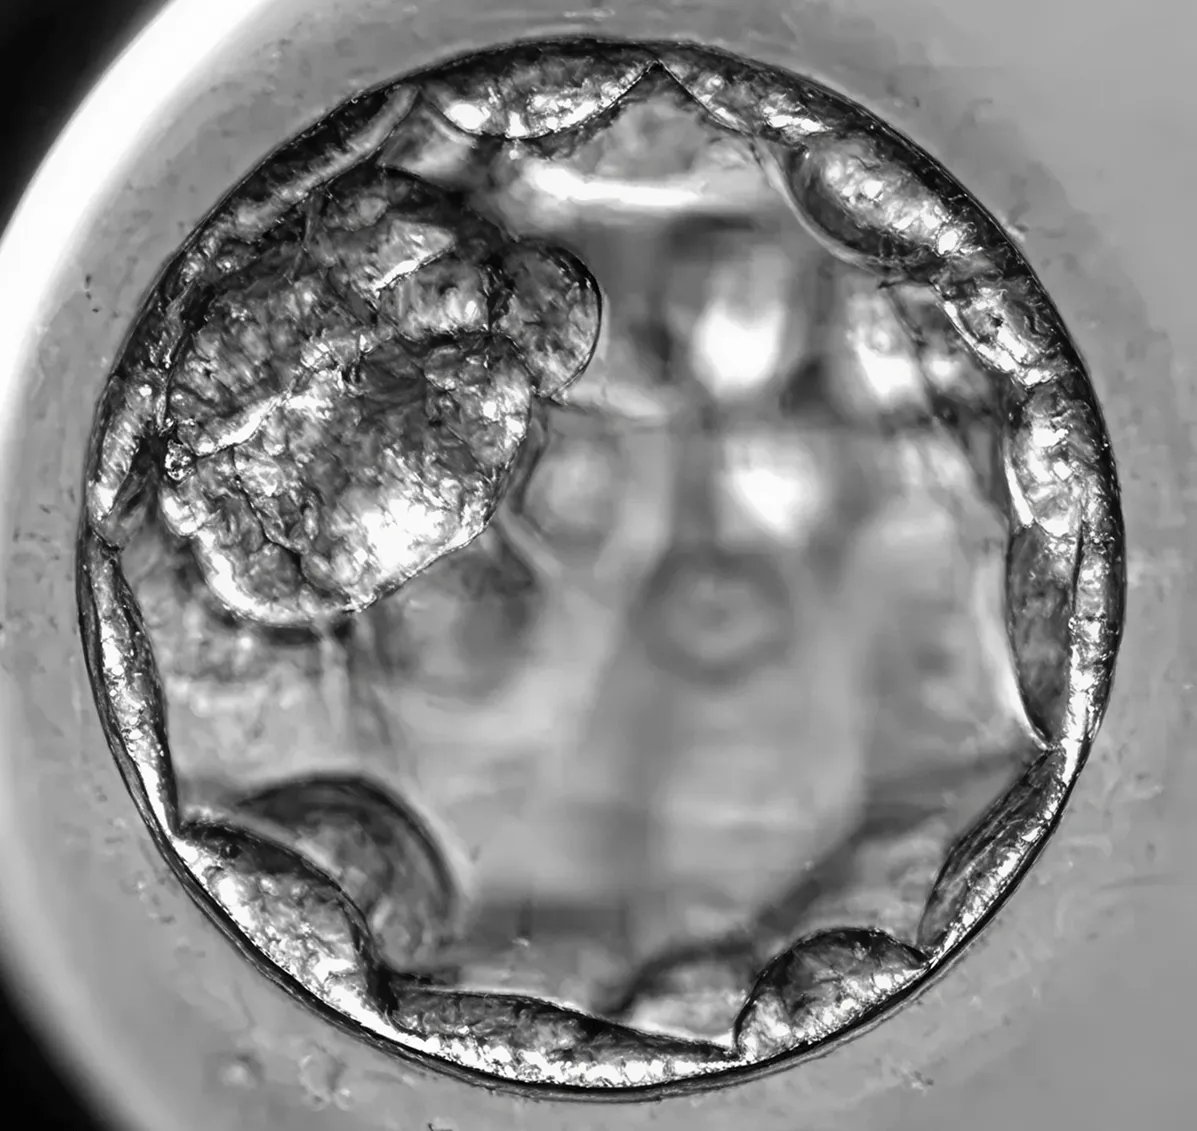

Излюпване и имплантационна готовност

Това е последния етап преди ембрионът да намери своето място в утробата. Обвивката му се е разкъсала и през отвора може да се показва част от бластоцистът, който вече е напълно готов да се прикрепи към маточната стена. Някои бластоцисти продължават да се разширяват и започват да се освобождават от обвивката.

Какво се вижда? – На екрана може да се види как бластоцистът „излиза“ от зоната си – това е т.нар. хачинг (hatching) – финалната подготовка преди имплантацията, момент, който винаги вълнува екипа и родителите.